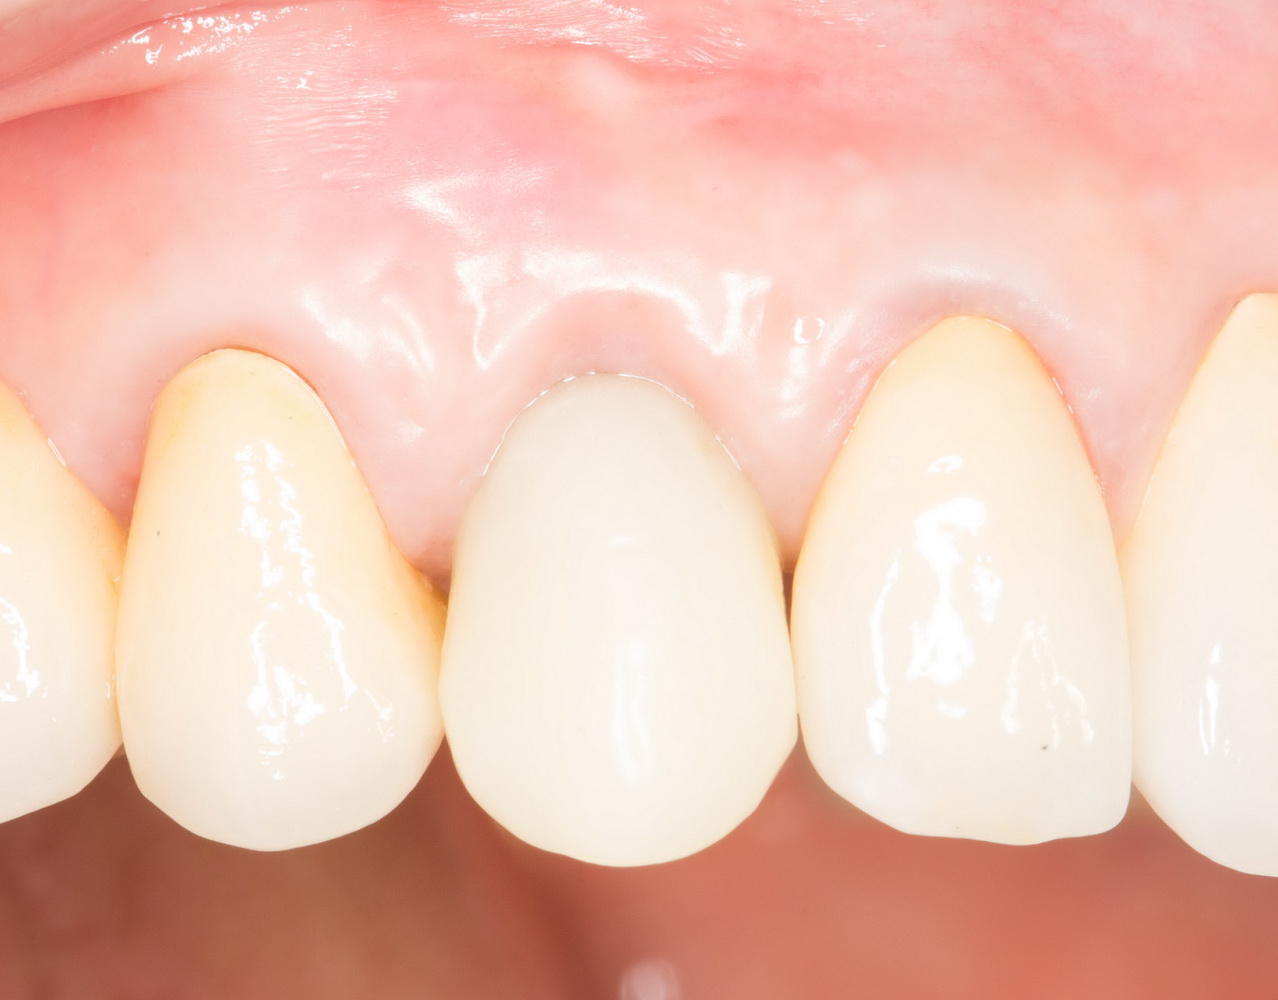

Через 3 месяца- внешний вид искусственного зуба:

Обратите внимание на состояние десны. Проведенные после установки импланта манипуляции позволили не только ее сохранить, но и увеличили объем. Формирование адекватных контуров и объемов слизистой оболочки, особенно в эстетически значимой зоне — еще одно назначение временных коронок на импланты. Все же, формирователи — штука стандартная, в то время как контуры десны как у разных людей, так и у разных зубов, свои — и под каждый зуб десну нужно готовить индивидуально.

Именно поэтому временное протезирование — важный этап всего лечения, который не рекомендуется пропускать. За редким-редким исключением.